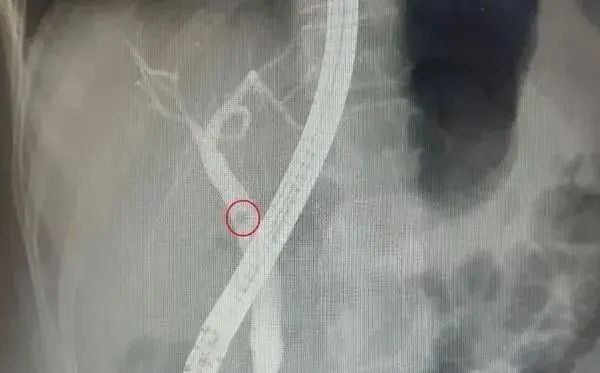

1名62歲陳姓男子日前突感上腹部疼痛、發燒、且尿液呈現深茶色,趕緊急診就醫。檢查後發現有黃疸、胰腺炎、總膽管有結石阻塞及擴大的情形,經醫師安排進行內鏡逆膽管造影術,並搭配內鏡下括約肌切開術和乳頭球囊擴張術後,將膽管內的結石全數清除並順利恢復出院。

過去膽管結石多以外科手術為主,現行則可採用內鏡逆膽管造影術來診斷及治療。其方式是使用內鏡從上消化道深入膽胰管開口,再注射顯影劑至膽道總管,若發現膽管中的結石,則可直接進行碎石與取石,無需再接受外科手術,可讓病人避免手術的痛苦並縮短術後的恢復期。

↑↑↑ 患者有總膽管結石阻塞的問題(紅圈處),經過內鏡(圖內中間的長型管子)診斷並同步清除碎石,順利恢復健康。